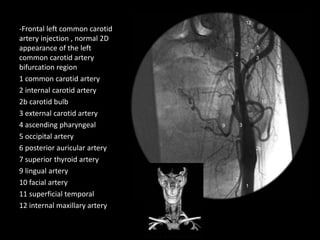

-Frontal left common carotid

artery injection , normal 2D

appearance of the left

common carotid artery

bifurcation region

1 common carotid artery

2 internal carotid artery

2b carotid bulb

3 external carotid artery

4 ascending pharyngeal

5 occipital artery

6 posterior auricular artery

7 superior thyroid artery

9 lingual artery

10 facial artery

11 superficial temporal

12 internal maxillary artery